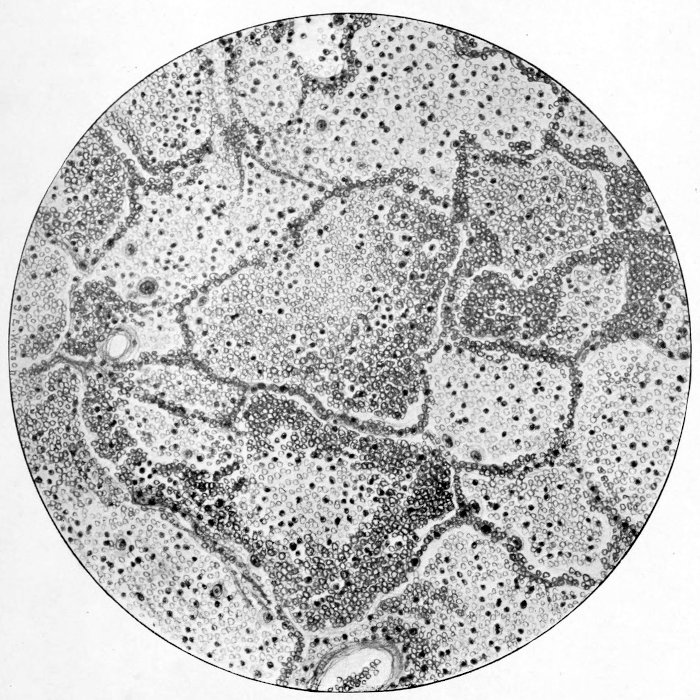

subscribe to our email newsletter to hear about new eBooks.